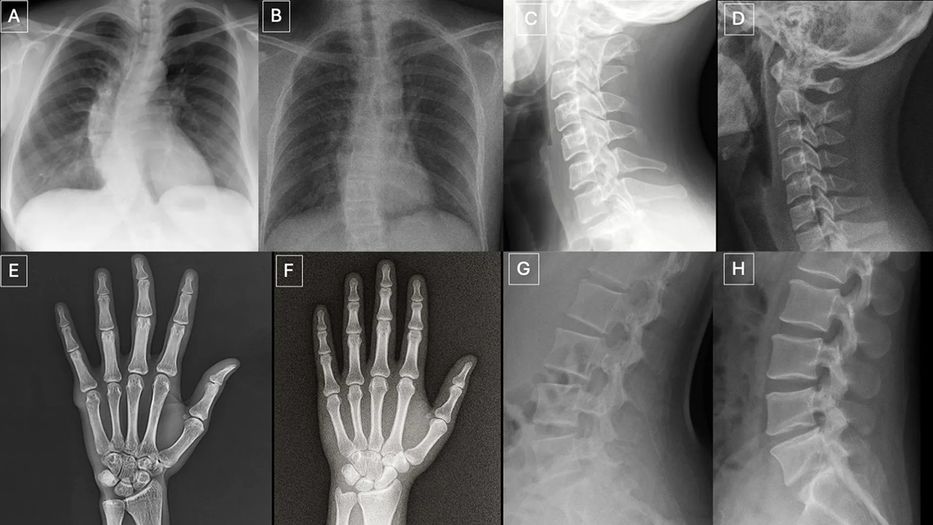

El doctor Tordjman describió con precisión qué hace que una radiografía deepfake sea sospechosa: “Las imágenes médicas deepfake a menudo lucen demasiado perfectas. Los huesos son excesivamente lisos, las columnas vertebrales antinaturalmente rectas, los pulmones demasiado simétricos, los patrones de vasos sanguíneos uniformes en exceso, y las fracturas aparecen inusualmente limpias y consistentes, a menudo limitadas a un solo lado del hueso”.

Esa perfección artificial, paradójicamente, es la principal pista.